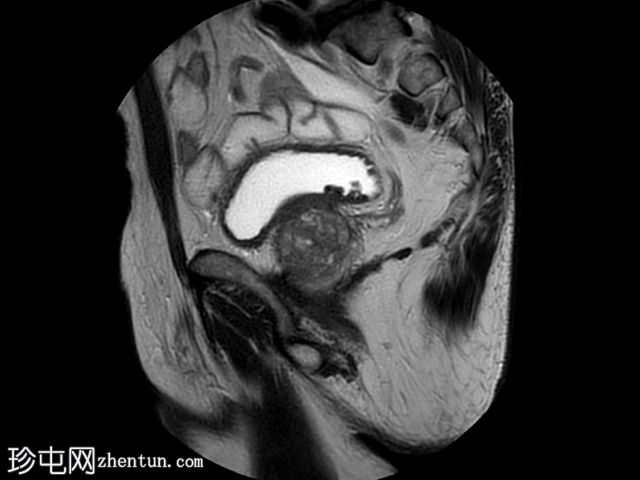

矢状位

T2加权像

在T1和T2加权像上,于膀胱底部及右下外侧面偶然发现一处呈蛇形缠绕状的低信号区。动态序列中可见快速对比增强,提示所有影像学表现均源于血管,信号缺失与动静脉畸形有关,该畸形至少由膀胱下动脉供血,并由同侧局部扩张的静脉回流。